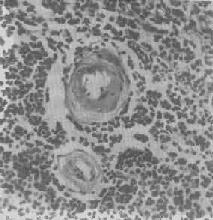

图1-17 肝细胞气球样变 病毒性肝炎时,肝细胞明显肿胀,胞浆疏松呈气球样 形态学:轻度肝脂肪变性时,肝肉眼观可无明显改变,或仅轻微黄染。如脂仿变性比较显著和广泛,则肝增大,色变黄,触之质如泥块并有油腻感。镜下,肝细胞内的脂肪空泡较小,起初多见于核的周围,以后变大,较密集散布于整个胞浆中,严重时可融合为一个大空泡,将细胞核挤向胞膜下,状似脂肪细胞(图1-18)。脂肪变性在肝小叶中的分布与其病因有一定的关系,例如肝淤血时,小叶中央区缺氧较重,故脂肪变性首先在此处发生。但长期淤血后,小叶中央区的肝细胞大多萎缩、变性或消失,于是小叶周边区肝细胞也因缺氧而发生脂肪变性。磷中毒时,肝细胞脂肪变性则主要发生于小叶周边区,这可能是由于此区肝细胞对磷中毒更为敏感的缘故。